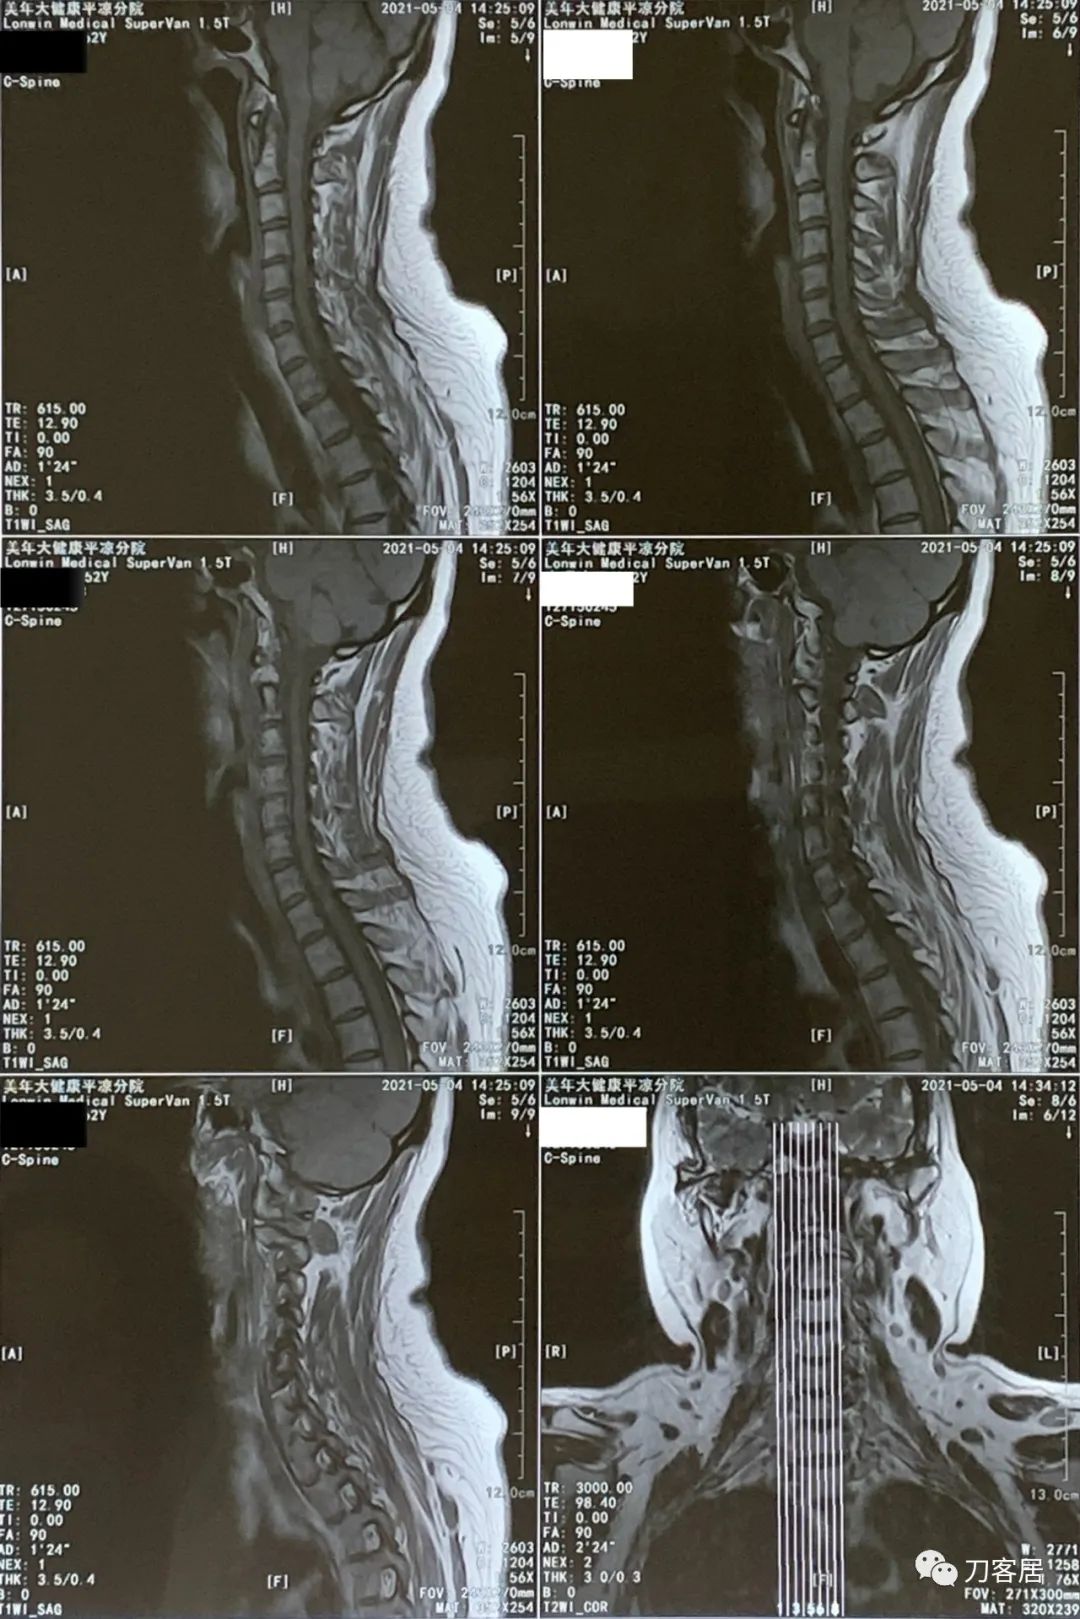

患者回当地后,一直没有再去医院就诊,不过到了2021年5月4日,患者在当地又做了一次颈椎磁共振检查。也就是经过抗骨质疏松治疗后,患者的临床症状应该都没了,恢复了正常的生活,从2020年8月19日到2021年5月4日,将近9个月,患者没有再去医院看病,到了2021年5月4日,患者又做颈椎磁共振,应该是患者自行停药,颈肩痛的症状又来了,然后到当地医院就诊,仍然考虑颈椎病,给开了颈椎磁共振检查。

图22. 20210504美年大健康平凉分院颈椎MRI01

图23. 20210504美年大健康平凉分院颈椎MRI02

图24. 20210504美年大健康平凉分院颈椎MRI03

图25. 20210504美年大健康平凉分院颈椎MRI04

图26. 20210504美年大健康平凉医院颈椎MRI报告